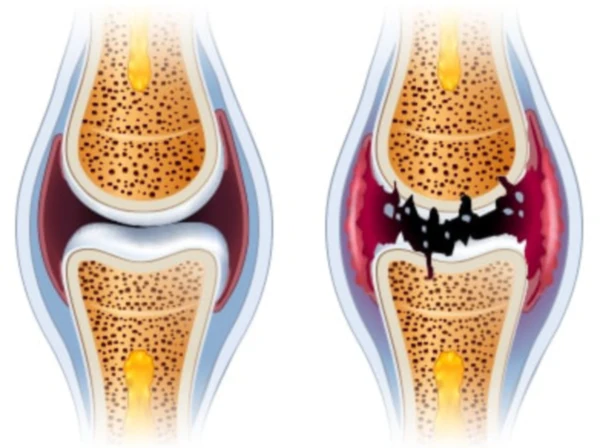

통풍은 주로 체내에 과다 축적된 요산으로 인해 발생합니다. 요산은 우리가 섭취하는 다양한 음식이 소화되어 최종적으로 대사된 후 혈액에 녹아 있다가 소변으로 배출되는 물질입니다. 일반적으로 혈액 내에서 요산은 정상 수준을 유지하며 배설됩니다. 그러나 통풍 환자는 혈액 내 요산이 과다하게 증가합니다. 이러한 과다 축적된 요산은 결정체로 변화하고, 이러한 결정체가 관절 내에 침착하여 염증을 일으킵니다.

통풍 환자는 대개 고요산혈증이라 불리는 혈액 내 요산이 정상치를 넘어선 상태를 가지고 있습니다. 그러나 고요산혈증이 있더라도 모든 고요산혈증 환자가 통풍 환자는 아니며, 무증상으로 고요산혈증인 사람이 더 많습니다. 통풍 관절염은 고요산혈증이 심하고 지속되는 경우에 발병할 가능성이 크며, 발병 확률은 기간이 길수록 높아집니다.